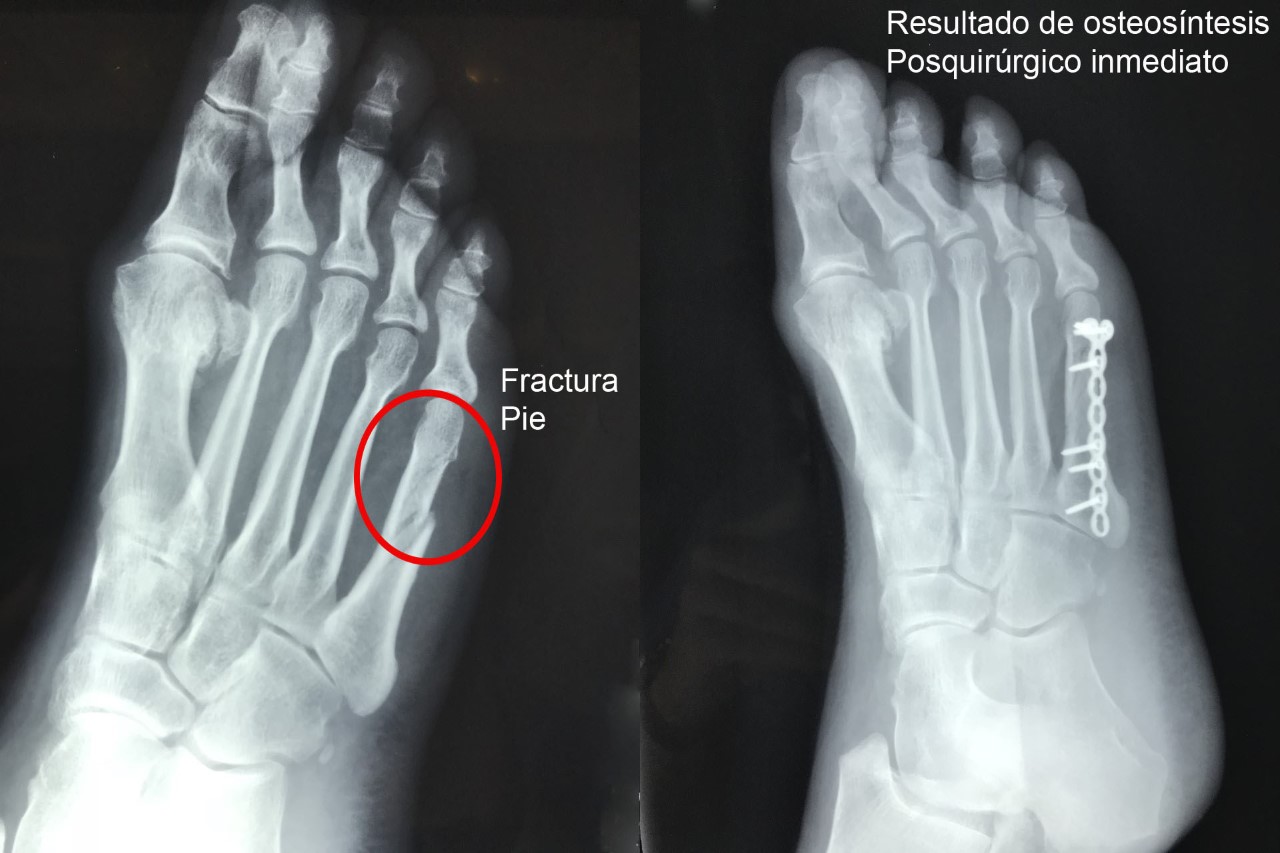

Una fractura ósea es la ruptura de un hueso, la cual puede presentarse por diversas causas y su tratamiento dependerá de la magnitud, sitio anatómico y de las enfermedades concomitantes. Algunas pueden manejarse de forma conservadora con solo inmovilización y hay otras que requieren de un tratamiento quirúrgico. A continuación, podrá ver algunos casos quirúrgicos, dando clic a la zona del cuerpo afectada.